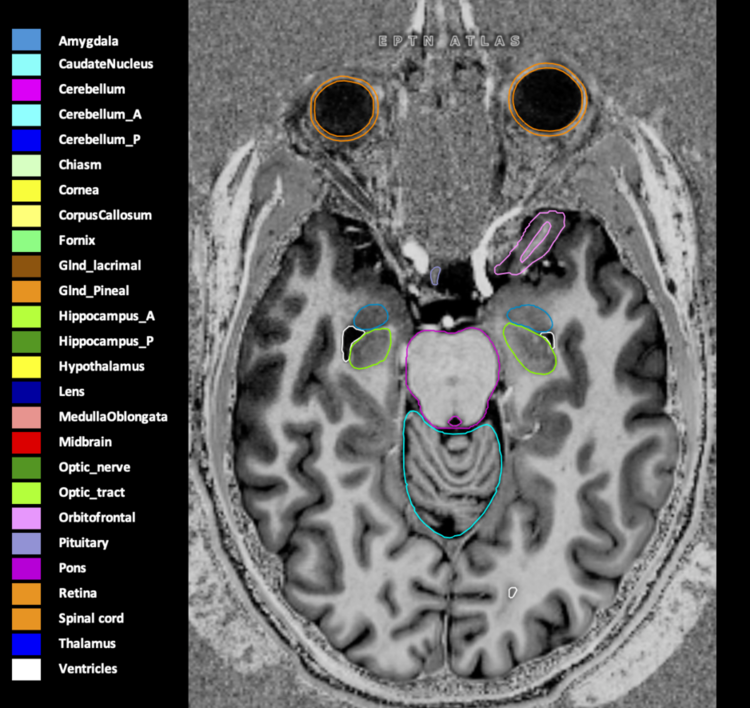

Eekers et al. have published an international neurological atlas for contouring of organs at risk in consensus with the European Particle Therapy Network (EPTN) in 2018 and an update in 2021. The purpose of this consensus atlas is to decrease inter- and intra-observer variability in delineating OARs relevant for neuro-oncology.

Included are all OARs known to be relevant for radiation-induced toxicity in neuro-oncology: brain, brainstem (midbrain, pons, medulla oblongata), chiasm, cerebellum (anterior & posterior), cochlea, cornea, hippocampus (anterior & posterior), hypothalamus, lens, lacrimal gland, optic nerve, pituitary, skin, and vestibular & semicircular canals. To further facilitate research on cognition, vision and radiological changes after irradiation of the brain, potential clinically-relevant OARs are included: amygdala, caudate nucleus, cerebellum (anterior & posterior), corpus callosum, fornix, macula, optic tract, orbitofrontal cortex, periventricular space (PVS), pineal gland, and thalamus.

Three-dimensional delineation of the 25 consensus OARs for neuro-oncology are shown on CT (WW/WL 120/40, 3000/600), 3T MR images, (T1Gd, T2FLAIR 1mm) and 7T MR (MP2RAGE 0.7 mm). All are presented in transversal, sagittal and coronal view.